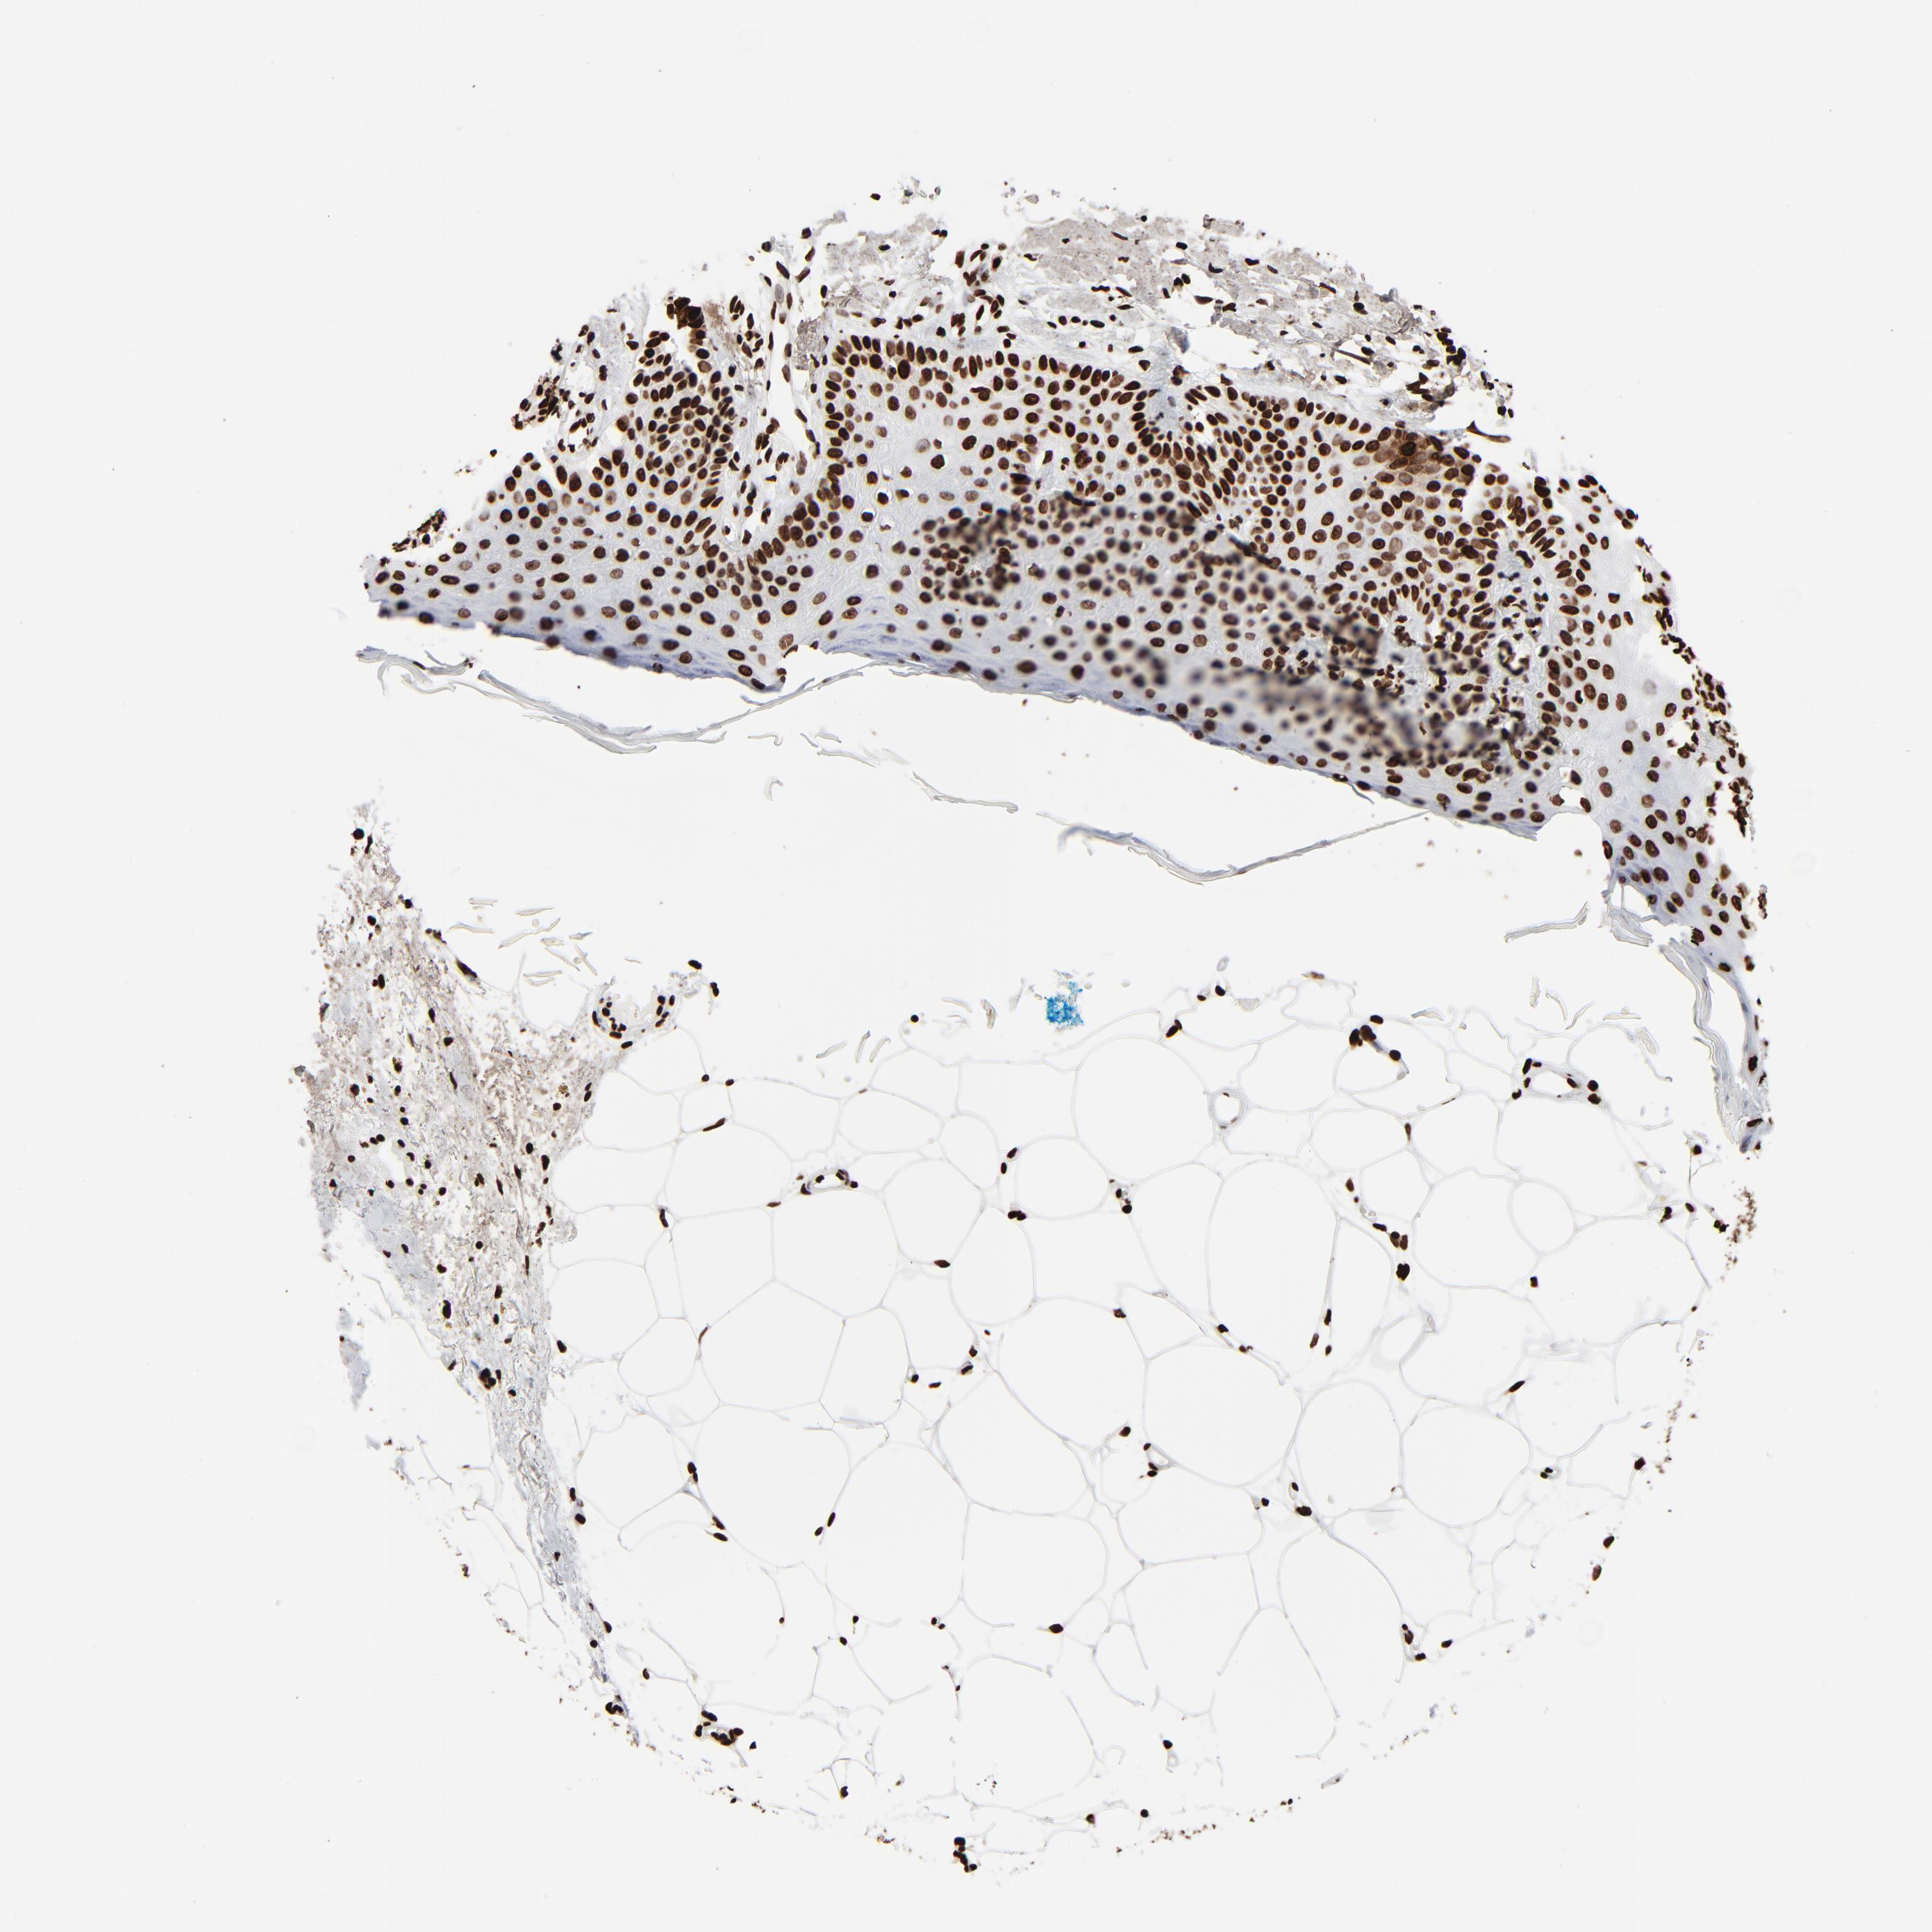

SKIN CANCER - Protein expressioni

A mouse-over function shows sample information and annotation data. Click on an image to view it in a full screen mode. Samples can be filtered based on level of antibody staining by selecting one or several of the following categories: high, medium, low and not detected. The assay and annotation is described here.

Each image is clickable and will lead to virtual microscopy that enables deeper exploration of all samples and also displays staining intensity scores, fraction scores and subcellular localization as well as patient and tissue information for each sample.

Antibody HPA042570

Basal cell carcinoma